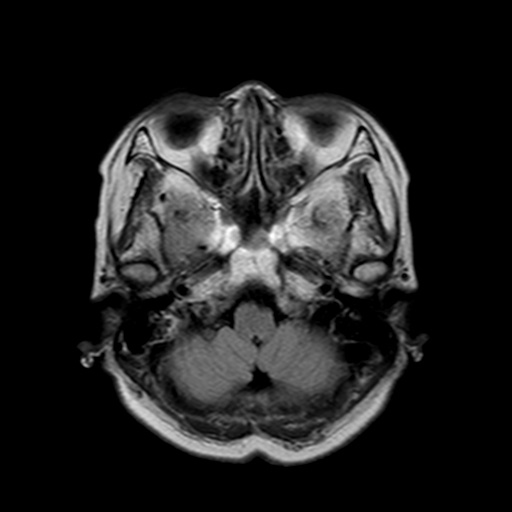

MRIは頭部の断層像で脳腫瘍や梗塞、出血がわかります。MRAは、血管のみ抽出した検査で、くも膜下出血、脳動脈瘤など脳内血管障害の発見に用います。

MRI検査

磁気と電磁波、それに水素原子の動きを利用して、体の断面を撮影する検査で、磁気共鳴画像検査ともいいます。詳細は省きますが、体内の水素が反応して発した信号を捕らえて、コンピューターで解析して画像にしたものです。

MRIではCT検査と同様、腫瘍の大きさや形、数などがわかります。また、MRAでは脳動脈瘤、脳梗塞、脳動静脈奇形、もやもや病、閉塞性動脈病変などの脳血管障害がわかります。脳ドックでは、くも膜下出血の原因となる脳動脈瘤のスクリーニング検査としてよく用いられています。